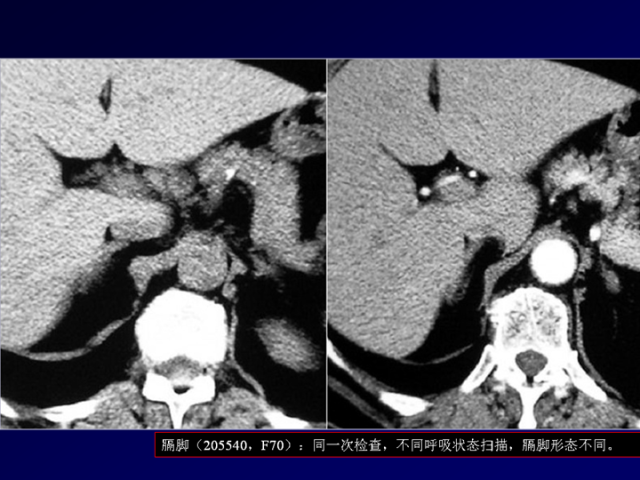

膈肌角解剖及常见变异

作者:王俭 上海长征医院